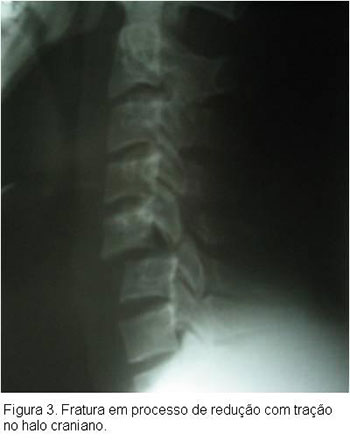

O tratamento do doente vítima de TRM inicia-se na abordagem inicial do paciente politraumatizado, segundo especificações do ATLS , tomando- se os cuidados necessários quanto a imobilização da coluna a fim de se evitar a progressão ou mesmo o surgimento de lesões neurológicas. Após a estabilização do paciente e realização diagnóstica de TRM com exame físico e exames secundários de imagem como Rx, TC ou RM cervical, deve-se proceder a estabilização da lesão cervical, geralmente com o uso de tração em halo craniano, até a programação do tratamento definitivo, que geralmente consiste na redução cruenta da fratura e fixação interna da mesma.Caso o paciente tenha sido atendido nas primeias 8 horas após o trauma deverá ser instituído a corticoterapia, salvo os pacientes com contra-indicações, segundo protocolo instituído pelo NASCISIII, a fim de evitar possíveis lesões secundárias à medula.Este protocolo consiste na aplicação de metilpredinisolona na dose de 30mg/kg ev na primeira hora, seguido de 5,4mg/kg/hora nas próximas 23hs, isto quando paciente chega ao hospital dentro de 3hs do trauma. Quando chega entre 3-8hs, manter esquema de 5,4mg/kg/hora por 48hs. Após 8hs não realizar corticoterapia. Contra-indicações para corticoterapia: gravidez, criança, imunossuprimido, fx exposta, infeccção grave ou risco de vida.Cuidados: monitorar PA, glicemia, e realizar proteção gástrica.